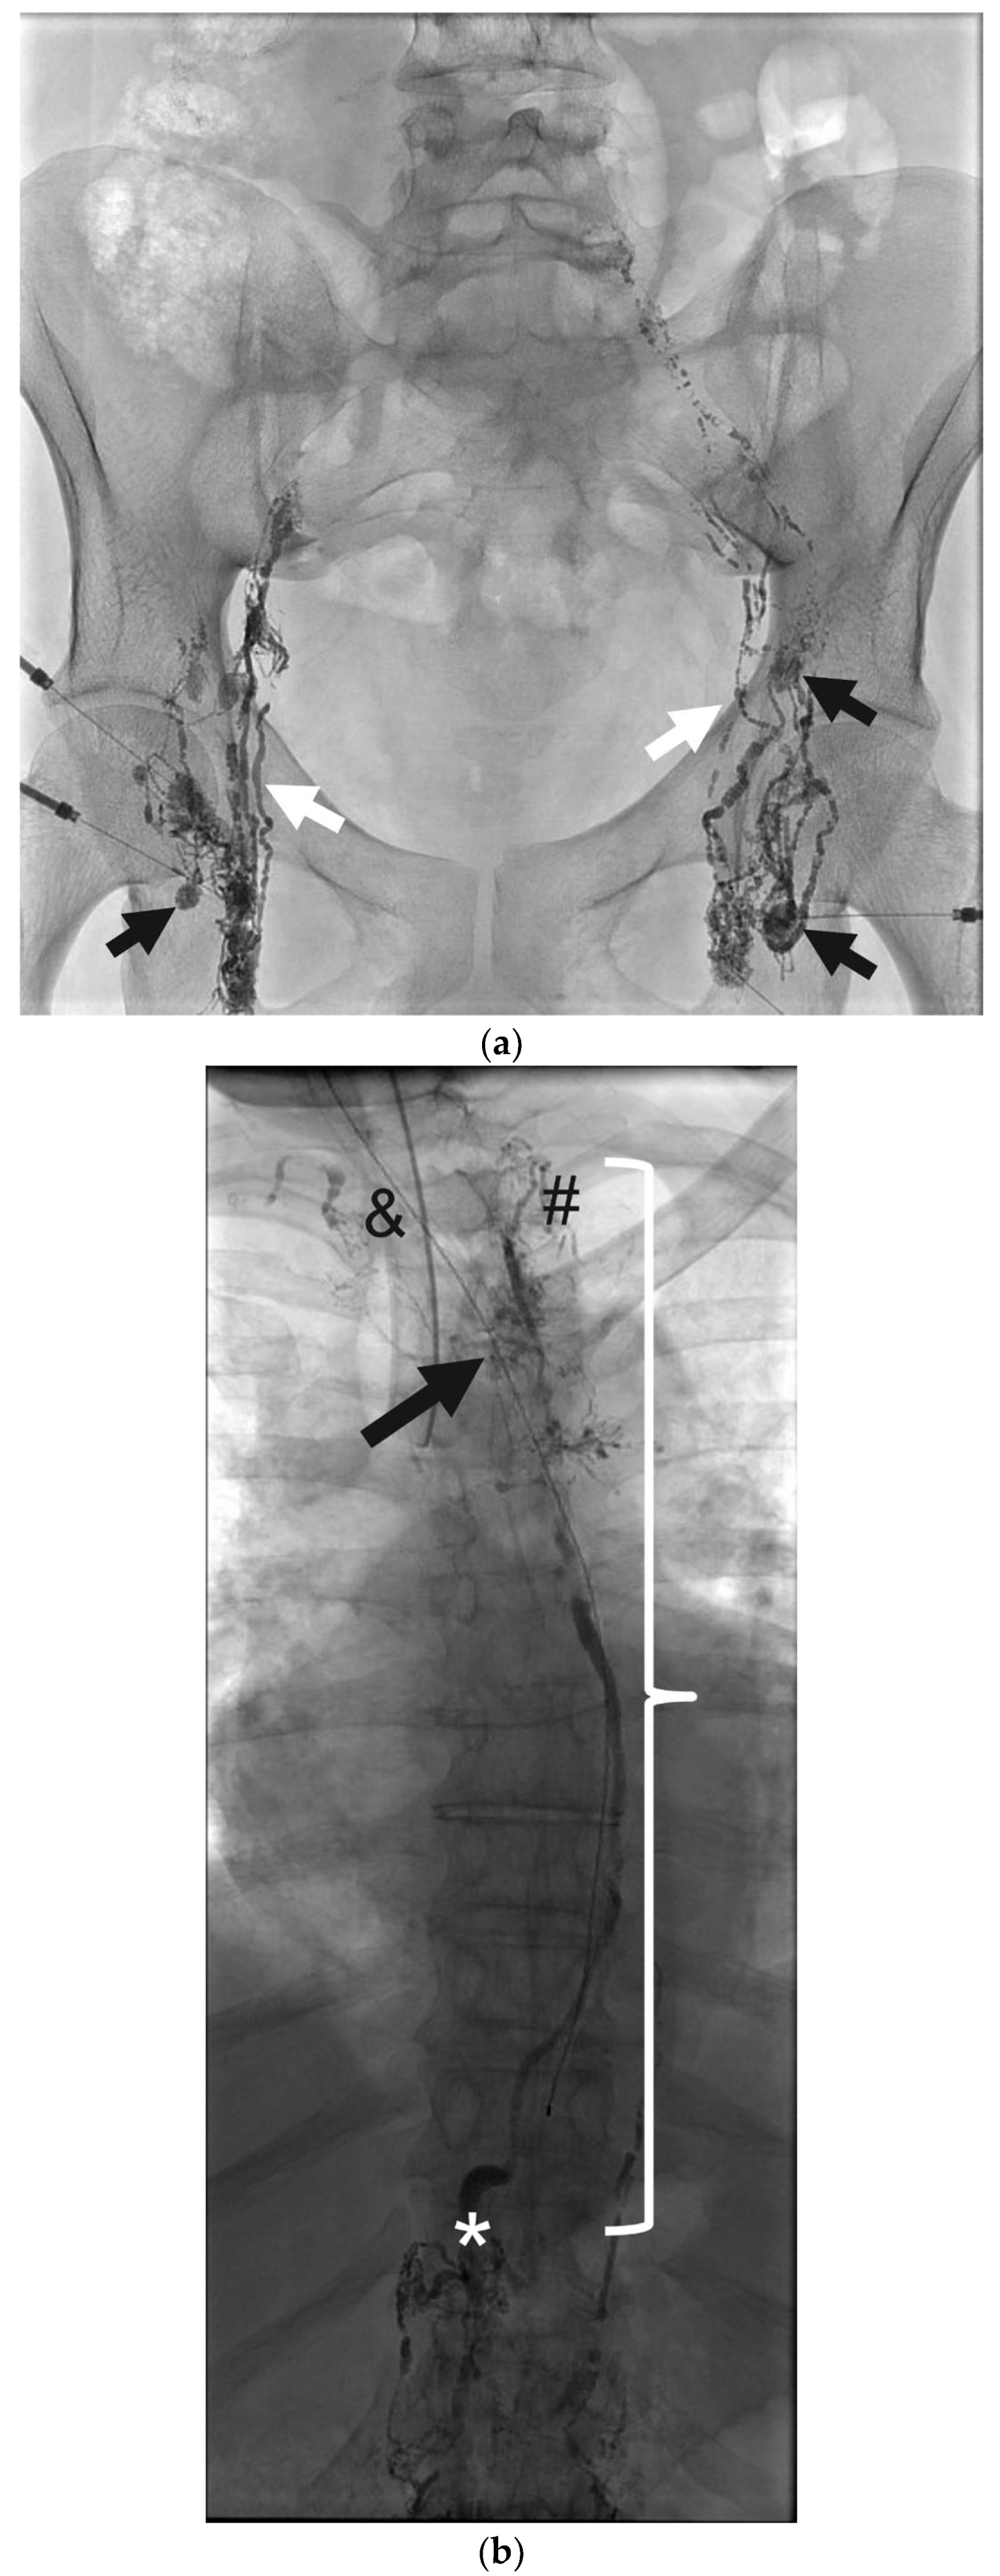

Figure 5. (a) Antero-posterior fluoroscopic lymphangiogram of a 34-day-old neonate with congenital chylothorax. Black arrows demonstrate a preferential flow through the dermal lymphatics without filling of the central conducting lymphatics, which would be expected over the midline of the spine, consistent with a central conducting lymphatic anomaly (CCLA). (b) is a coronal 3D reformat from cone-beam CT images. The white arrows correspond to dermal lymphatics without lymphatic channels in the central midline.